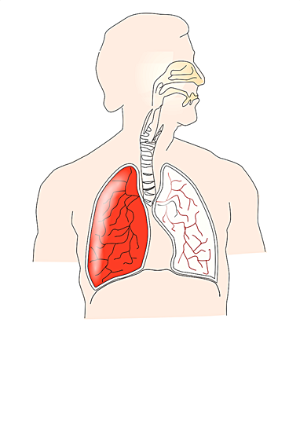

폐렴을 유발하는 폐렴구균은 약 40%의 일반인이 이미 가지고 있는 것으로 알려져 있습니다. 대부분의 경우 평소에는 문제가 되지 않지만, 면역력이 감소하게 되면 폐렴이 발병할 수 있습니다. 이렇게 되면 폐에 산소공급이 부족해져 청색증이 나타날 수 있습니다. 이는 손, 발, 입술 등 피부가 얇은 부위가 파랗게 변하는 증상을 말합니다.

폐렴의 증상 중 하나로 분류되는 급성폐렴은, 폐렴으로 인해 산소공급이 원활하지 않게 되면서 피부색이 창백해지거나 경직 등의 마비 증상이 발생할 수 있습니다. 이런 증상이 나타나면 즉시 응급실로 이동해야 합니다. 마비 증상은 매우 무서운 증상으로 느껴질 수 있으므로, 이런 증상이 나타나면 즉시 의료진의 도움을 청해야 합니다.